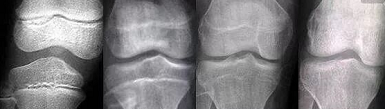

做骨龄检测

在孩子的成长过程中,父母应该时刻注意孩子的骨龄,最好每3-5年测试一次骨龄。这是一种常用的临床方法,可以准确地显示儿童的年龄和肌肉发育。如果测量的数据差距是±3个月,属于正常发育,如果差距超过一年,需要医生干预。